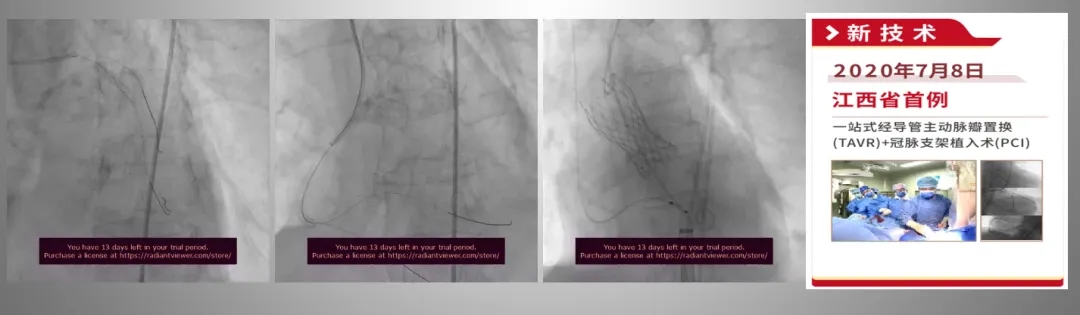

彭小平教授进一步指出,我国接受TAVR的患者群体仍以外科手术风险较高的老年人为主,且多合并冠心病,因此对TAVR联合PCI的需求较为突出。此外,我国患者中二叶式主动脉瓣占比高,瓣膜钙化程度重,这些解剖特点使得术中更倾向于选择偏小型号的瓣膜,并采用高位释放的植入策略。相较于球扩式瓣膜,自膨胀式瓣膜的瓣架较长,致使TAVR术后若需行PCI,导丝穿过人工瓣膜金属假体的操作难度显著增加,目前在我国实际临床实践中实施TAVR术后PCI仍具有较大挑战。因此,分站式与一站式TAVR+PCI手术策略现阶段被认为是更适应中国患者特点的治疗路径。

82岁女性,重度主动脉瓣狭窄伴冠心病(一站式)